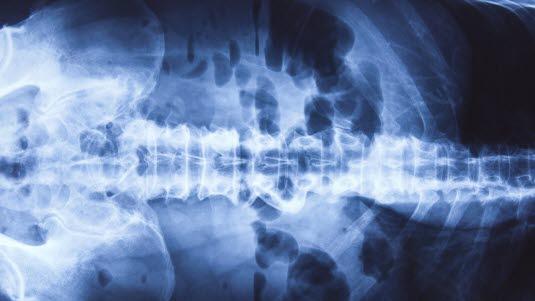

Røntgen oversikt bukhulen

Røntgen oversikt av bukhulen tas uten bruk av kontrast. Undersøkelsen anvendes som et diagnostisk hjelpemiddel ved akutte sykdommer i bukhulen.

Organer i bukhulenBukhulen består av mange organer. De største er magesekk, tynntarm, tykktarm, lever, milt, bukspyttkjertel, nyrer, urinveier, urinblære. Alle disse organene består av såkalt bløtvev, slik at ingen av dem vil i detalj kunne fremstilles på røntgenbilder uten bruk av kontrast. Likevel kan oversiktsbilder av bukhulen gi nyttig informasjon da luft og eventuelt avføring i tarmen gir informasjon.

Væskespeil er et fenomen som røntgenlegen studerer nøye. Det dreier seg om tarmavsnitt som er fylte med både luft og væske. Det vil da dannes væskeoverflater som kan ses på bilder tatt med horisontal stråleretning.

Det er røntgen oversiktsbilder av bukhulen som tas uten bruk av kontrast. Undersøkelsen anvendes som et diagnostisk hjelpemiddel ved akutte sykdommer i bukhulen som nyrestein, akutt tarmtilstopning av fordøyelseskanalen, oppfylninger eller sprukne organer. Røntgen oversikt bukhulen er ofte en forundersøkelse før mer omfattende undersøkelser. Den kan også gi informasjon om størrelse, form og posisjon til lever, milt og nyrer.

Ved en normal undersøkelse påvises normale organer. Det vil ses endel luft både i magesekken og i tykktarmen. Tolvfingertarmen (første del av tynntarmen) inneholder også ofte luft og væskespeil. Tynntarmen videre kan ev. også inneholde litt luft. Enkelte korte væskespeil i tynn- og tykktarm kan være normalt. Det skal ikke være luft i bukhulen utenom magetarmkanalen, men hvis det går hull på kanalen et eller annet sted, f.eks. magesekken, kan fri luft påvises som tegn på alvorlig sykdom. Det er fare for utvikling av bukhinnebetennelse (peritonitt), som kan være livstruende.